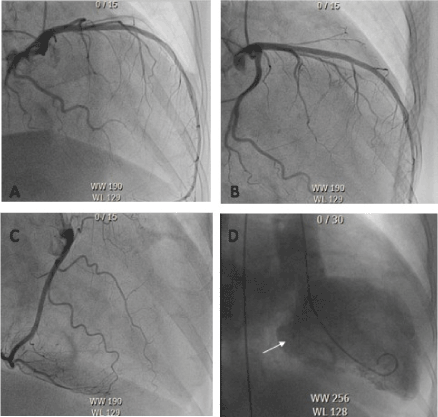

Electrical cardioversion was not successful. The coronary angiography excluded any form of coronary vessel disease (Figure 3). For further investigation, a cardiac Magnetic Resonance Imaging was performed and showed a late gadolinium enhancement with circumferential subendomyocardial enhancement (Figure 4) with like a Loffler-Endocarditis. Therefore, a treatment with oral corticosteroids was started. Furthermore, a myocardbiopsy was accomplished. The Massom Trichom Stain and the SM-Actin Immunhistology showed the pathology of an endomyocardial fibrosis without typical signs of a Loffler-Endocarditis (Figure 5). The corticosteroid therapy was stopped, and heart failure medication was intensified via Sacubitril/Valsartan (Entresto®). Because of the highly reduced ejection fraction, irreversible fibrotic stage and the risk of sudden cardiac death caused by ventricular arrhythmia, a cardiac defibrillator was implanted. After recompensation the transthoracic echocardiography showed an improvement of the mitral and tricuspidal regurgitation and a slowly decreasing NT-proBNP of 2375ng/l.

Figure 3.Coronary angiography: Left coronary artery (A+B) and the right coronary artery (C).

Leavo-cardiography (D) with mitral-regurgitation (arrow)